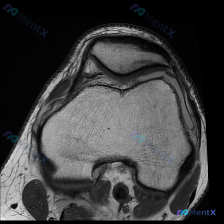

今天碰到一个很典型的「临床-影像矛盾」病例,整理出来和大家一起讨论一下。 病例核心信息 问题:临床高度怀疑膝关节软骨异常,仅提供1张膝关节MRI-T1序列轴位影像(髌股关节层面),要求读片分析。 影像读片结果: 1. 骨性结构:股骨远端、髌骨骨皮质连续,软骨下骨光滑,骨髓脂肪信号均匀,未见异常信号灶...